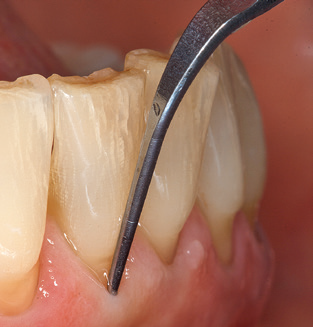

Good illumination of the working field facilitates the process considerably. The system used by the authors achieves this thanks to a 5x LED ring integrated in the handpiece. Naturally, a range of working tips for different indications is also offered. A straight, universally employable tip is the basic instrument required for machine cleaning of natural teeth (Fig. 5a and b). Curved tips, which allow access to exposed furcations, are also available for hard-to-reach areas in the posterior region (Fig. 6).

Of course, working tips for the cleaning of implant surfaces are also indispensable for SPT in patients fitted with implants. The implant cleaning attachment on the system used here is characterised by its tapered, hexagonal design. This design allows light, atraumatic penetration of the peri-implant pocket and displays a good cleaning performance (Fig. 7).